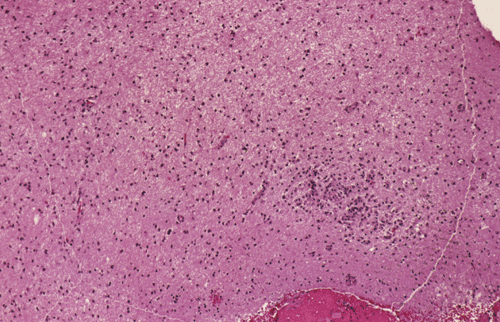

Streotactic biopsy yielded several cores of tissue. On scanning magnification, there are multiple small lymphocytic collections (Ž in Panel C) in the white matter. On higher magnification, these areas contain mostly lymphocytes without atypia. These collections appear to be angiocentric and are often admixed with some foamy macrophages (Panel  D and E). On LFB/PAS stain, multiple small, irregular areas of angiocentric pale staining are present (Panel F and G). On high magnification, these areas are featured by infiltration by foamy macrophages and lymphocytes and myelin loss (Panel  H). On Bielschowsky stain, the axons in these pale areas are largely preserved. Immunohistochemistry on GFAP demonstrates multiple stellate reactive astrocytes (Panel J). The macrophages and lymphocytes are also well demonstrated by immunohistochemistry for CD68 and LCA respectively (Panel  K and L).

The histopathology of inflammatory demyelinating pseudotumors is very similar to that of acute disseminated perivsnous encephalomyelitis or the classic type of ADEM. In essence, there is perivenous chronic inflammatory cell infiltration accompanied by infiltrating, foamy macrophages with an angiocentric distribution. Loss of myelin and relative preservation of axon fibers must be demonstrated before a diagnosis of demyelinating process is made. The loss of myelin can be well demonstrated by special stains for myelin with the Luxol fast blue based stains as one of the most commonly used stains. Relative preservation of axons can be sell demonstrated by silver stains such as Bodian stain, Bielschowsky stain, and also immunohistochemistry for moderate and high molecular weight neurofilament proteins. The pathologic highlights on separating inflammatory demyelinating lesions from mimicking lesions have been well described by Zagzag et al. 8. Other inflammatory lesions, particularly viral infectons, must also be ruled out. Keen observations particularly for nuclear inclusion bodies, immunohistochemistry for specific viral agents, and laboratory studies of the cerebral spinal fluid (CSF) and blood are often helpful. Identification of oligoclonal bands on electrophoresis of CSF is a strong suggesting of a demyelinating process.